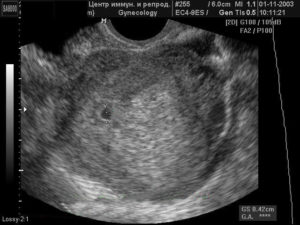

Обследование на УЗИ

Ультразвуковое исследование на данном сроке, естественно, не покажет наличие эмбриона. Но его проводят для своевременного обнаружения кист и опухолей в полости матки.

Также оно может показать истончение эндометрия, способное нарушить процесс имплантации оплодотворённой яйцеклетки и стать причиной невынашивания беременности и бесплодия.

Кроме того, УЗИ позволяет оценить рост фолликулов и степень зрелости яйцеклетки.

УЗИ плода на 1 неделе беременности

УЗИ плода на первой акушерской неделе беременности, как вы сами поняли из схемы выше, не делают. Это совершенно бессмысленно до оплодотворения и полового акта с целью зачатия между будущими родителями. Однако ультразвуковое исследование допустимо на сроке – первая эмбриональная неделя беременности (соответствующая третьей акушерской) с целью подтвердить беременность.

УЗИ развития плода

На первой неделе беременности, проведя ультразвуковое исследование, в полости матки можно увидеть утолщенный слой эндометрия, который готовится к прикреплению оплодотворенной яйцеклетки.

Проводят также обследование яичников, с целью определить в каком из них созрел доминантный фолликул. Он имеет вид округлой темной полости и по размеру отличается от других.

Зреющий фолликул имеет неправильную форму, на нем появляется яйценосный бугорок, который есть основой для будущей яйцеклетки.Желтое тело выглядит как темное пятно с неправильными контурами. Оно развивается в том месте, где лопнул фолликул, и вырабатывает прогестерон.